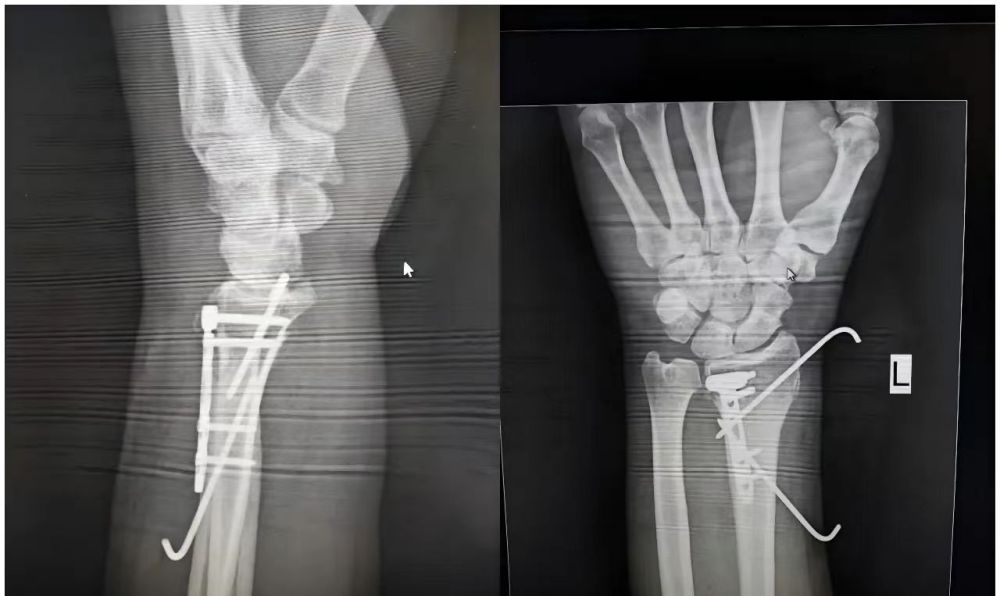

10月31日无棣县人民医院李涛专家团队,深入医共体成员单位——小泊头镇卫生院,成功开展了一例“左侧桡骨切开复位内固定术”,这是卫生院外科开诊以来第207例手术,不仅是对小泊头镇卫生院医疗技术水平的又一次肯定,更是医共体建设模式下优质医疗资源下沉基层、惠及百姓的生动实践。通过医共体的构建,上级医院的专家和技术力量得以有效下沉,使得农村地区的群众无需远行,在家门口的卫生院就能享受到高质量的医疗服务,真正实现了“大病不出镇”的就医愿景。